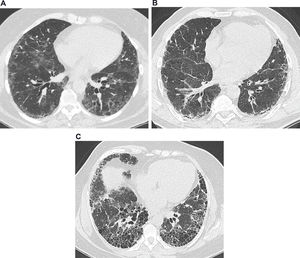

Common features on high-resolution computed tomography in interstitial lung diseases. (a) Images from a 63-year-old female presenting a nonspecific interstitial pneumonia pattern. There are predominant areas of ground-glass opacities, with some traction bronchiectasis and cortical interlobular septal thickening. (b) Images from a 61-year-old male with idiopathic pulmonary fibrosis. There are diffuse areas of interlobular septal thickening, predominantly in the cortical lung zones. (c) Images from a 56-year-old female with idiopathic pulmonary fibrosis. There are extensive areas of honeycombing, with some interlobular septal thickening.

Ground-glass opacityOn computed tomography (CT) imaging, GGO presents as a dense area of increased opacity within the lungs that conserves bronchial and vascular margins (Figure 1A) 9. GGO is less hazy than consolidation, in which bronchovascular margins cannot be distinguished. GGO can be due to the partial filling of airspaces, interstitial thickening (as a result of fluid, cells, and/or fibrosis), the partial collapse of alveoli, an increased capillary blood volume, or a combination of these, whereas all are related to the common partial displacement of air 9. Good interobserver agreement has been reported in the detection of GGO (kappa value, 0.78-0.90) 10.

A reticular pattern is defined as a collection of several small linear opacities that resemble a net-like aspect (Figure 1B) 9. The components of a reticular pattern are clearly observed on thin-section CT, and they can represent interlobular septal thickening, intralobular lines, or the cyst walls of honeycombing. This finding is usually associated with ILD, but congestion and infections (e.g., viral) are also important differential diagnoses 9.

HoneycombingHoneycombing is defined as clustered cystic airspaces that are usually subpleural with well-defined walls and diameters ranging from 0.3-1 cm, reaching 2.5 cm is rare cases (Figure 1C) 9. Commonly considered specific for IPF, honeycombing is an essential criterion for UIP diagnosis, and the terminology should be used carefully as it may directly influence patient management 11. Centrilobular emphysema, traction bronchiectasis, and cystic lung disease should be included in the differential diagnoses. Interobserver agreement for honeycombing is moderate (kappa=0.59±0.12). In a study by Watadani et al., there was disagreement on the identification of honeycombing in 29% of cases due to the co-existence of traction bronchiectasis, large cysts, and overlapping pulmonary emphysema 12.

Traction bronchiectasisTraction bronchiectasis and bronchiolectasis represent nonuniform bronchial and bronchiolar dilatation, respectively (Figure 1A) 9. Dilated airways can also present as cysts (bronchi) or microcysts (bronchioles in the lung periphery). In IPF, traction bronchiectasis is better explained as a result of bronchiolar proliferation instead of utter mechanical traction 13. Recent studies have suggested that traction bronchiectasis and honeycombing are parts of a spectrum of the presentation of a singular and continuous mechanism of bronchiolar dysplastic proliferation in IPF 13,14. On the other hand, in nonspecific interstitial pneumonia (NSIP), bronchocentricity is predominant, and traction bronchiectasis is exclusively surrounded by fibrotic tissue, characteristics that suggest the mechanical traction as the main component in the development of traction bronchiectasis in NSIP 13,14. Interobserver agreement for traction bronchiectasis is moderate, with kappa舁values ranging from 0.24 to 0.42 11.